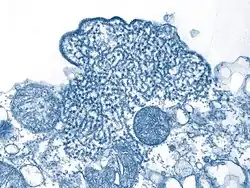

Das Nipah-Virus (NiV, auch NIPV, Spezies Henipavirus nipahense) ist ein Virus aus der Familie Paramyxoviridae,[3][4] das beim Menschen eine häufig tödlich verlaufende Gehirnentzündung (Enzephalitis) auslösen kann. Das Nipah-Virus tritt insbesondere in Südasien und Südostasien auf und kann durch Kontakt mit Körperflüssigkeiten und -ausscheidungen infizierter Tiere, Menschen oder Reservoirwirte oder dem Verzehr von kontaminierten Lebensmitteln übertragen werden. Reservoirwirte sind fruchtfressende Flughunde der Gattung Pteropus, die in Süd- und Südostasien sowie auf Madagaskar vorkommen. Diese Flughunde scheiden das Virus z. B. über Urin und Speichel aus und übertragen es in der Regel auf andere Tiere (insbesondere Schweine), die es auf den Menschen weiterübertragen.[5]

Das Nipah-Virus bildet zusammen mit dem eng verwandten Hendra-Virus die Gattung Henipavirus in der Familie der Paramyxoviridae. Es wurde erstmals 1999 im Zuge der Untersuchungen des Ausbruchs in Malaysia und Singapur charakterisiert.[6] Das isolierte Virus war morphologisch dem kurz zuvor in Australien entdeckten Hendra-Virus sehr ähnlich, jedoch im Krankheitsverlauf und seiner Antigenität doch von diesem verschieden. Es wurde daher vor einer endgültigen Benennung zunächst als Hendra-like Virus bezeichnet. Das neue Virus erhielt seinen taxonomischen Namen in Anlehnung an den kleinen Ort Kampung Teluk Nipah auf der malayischen Insel Pangkor, wo die Epidemie von 1998 besonders hohe Infektionszahlen aufwies und das Virus aus einem von dort stammenden Patienten isoliert wurde.